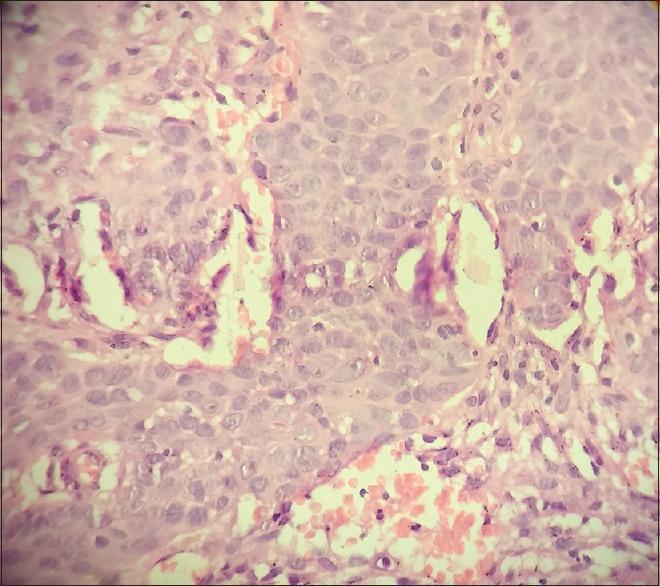

Primary Diffuse Large B-cell Lymphoma of the Breast: A Rare Case and Review of Literature.

Indian J Med Paediatr Oncol. 2017 Apr-Jun;38(2):244-247. doi: 10.4103/ijmpo.ijmpo_112_16.